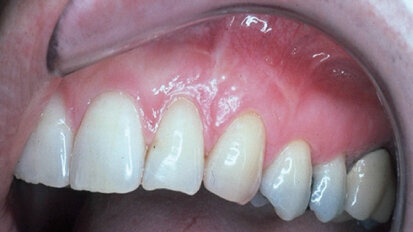

Cosmetic periodontal surgery: Multiple gingival graft techniques (Part 2)

In today’s new information age, patients want a better quality of life. They want to keep their youthful, brighter-appearing smile more than ever; keep ...